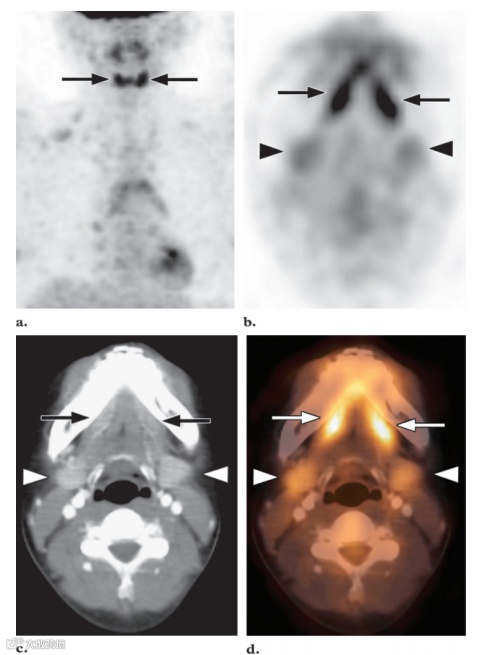

图3. MIP FDG PET 图像 (a) 和横向FDG PET (b)、CT (c) 和融合PET/CT (d) 图像显示舌下腺的摄取显著增加(箭头),颌下腺的摄取轻度增加(b-d中的箭头)。

最强烈的FDG活性存在于正常的大脑皮层和基底神经节中,因为大脑依赖糖酵解代谢作为能量来源(图1)。大脑代谢可能占整个空腹状态下的身体代谢的20%。大脑的总吸收量约为注射剂量的FDG的6%。由于韦氏环淋巴组织的生理活动,腺样体、扁桃体和舌根通常会出现轻度至中度的摄取。然而,在韦氏环中可以看到明显的强烈摄取(图2),尤其是在儿童中,因为这些淋巴组织的生理活性很高,在6-8岁达到峰值,此后逐渐减弱。在儿童体内这些区域的正常FDG摄取并不一定意味着有疾病。通常情况下,生理性扁桃体和腺样体摄取的对称模式有助于识别这种正常变化。软腭也可显示强烈的放射性示踪剂摄取。唾液腺的摄取情况各不相同,但通常为轻度至中度(图3)。有研究报告称,约51%的患者腮腺有轻度至中度摄取,腮腺高度摄取约14%。颌下腺和舌下腺的摄取情况各不相同,阳性率分别为53%和72%。化疗或放射治疗后也可见唾液腺摄取量弥漫性增加。由于近期手术或放射治疗后出现急性炎症,唾液腺对FDG的摄取可能不对称。然而,放射治疗最终可能导致患侧摄取减少。